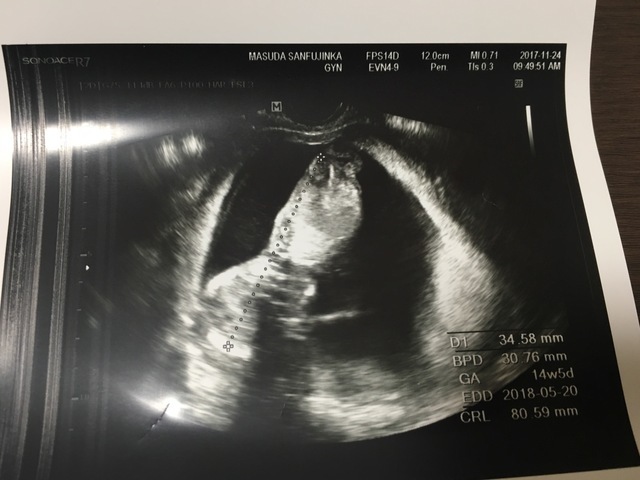

14週5日(14w5d・男の子)|nako08 さん(27歳)

エコー写真撮影時のエピソード:

悪阻は全体的に軽かったが、頭痛がずっとしていた。この日は午後から体調が悪くなり何を食べても吐いてしまい、ずっと寝ていた。

この3D?4D?写真が赤ちゃんをちゃんと写せた最初で最後の写真。その後からはずっと顔の前に手があったり、隙間が無くて3D?4D?写真を撮ってもらえなかった。

だからちゃんと全身が見えて、はっきり写ってるこの写真は宝物。